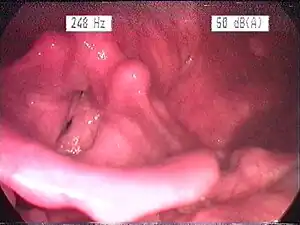

| Endoscopic image of an inflamed larynx caused by acid reflux | |

Visual diagnosis

The larynx itself will often show erythema (reddening) and edema (swelling). This can be seen with laryngoscopy or stroboscopy (method depends on the type of laryngitis).[7]: 108 Other features of the laryngeal tissues may include

- Redness of the laryngeal tissues (acute)

- Dilated blood vessels (acute)

- Thick, yet dry laryngal tissue (chronic)

- Stiff vocal folds

- Sticky secretions between the vocal folds and nearby structures (the interarytenoid region)